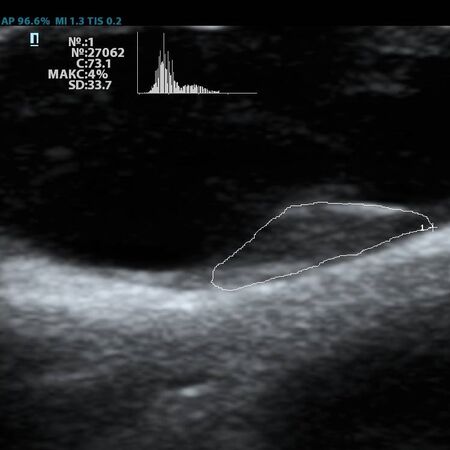

Современное решение – компьютерный анализ структуры бляшки. Ультразвуковая система экспертного класса Mindray DC-8 способна провести программный анализ полученного изображения бляшки и дать количественную оценку её структуры. Для этого используется показатель GSM – Grey Scale Median. Прибор рассчитывает медиану по показателям серой шкалы в выделенной зоне и выдает данные в виде графика распределения эхогенности и числовых данных для количественной оценки. Таким образом, исследование становится более объективным и воспроизводимым, снижается зависимость от оператора (человеческого фактора).